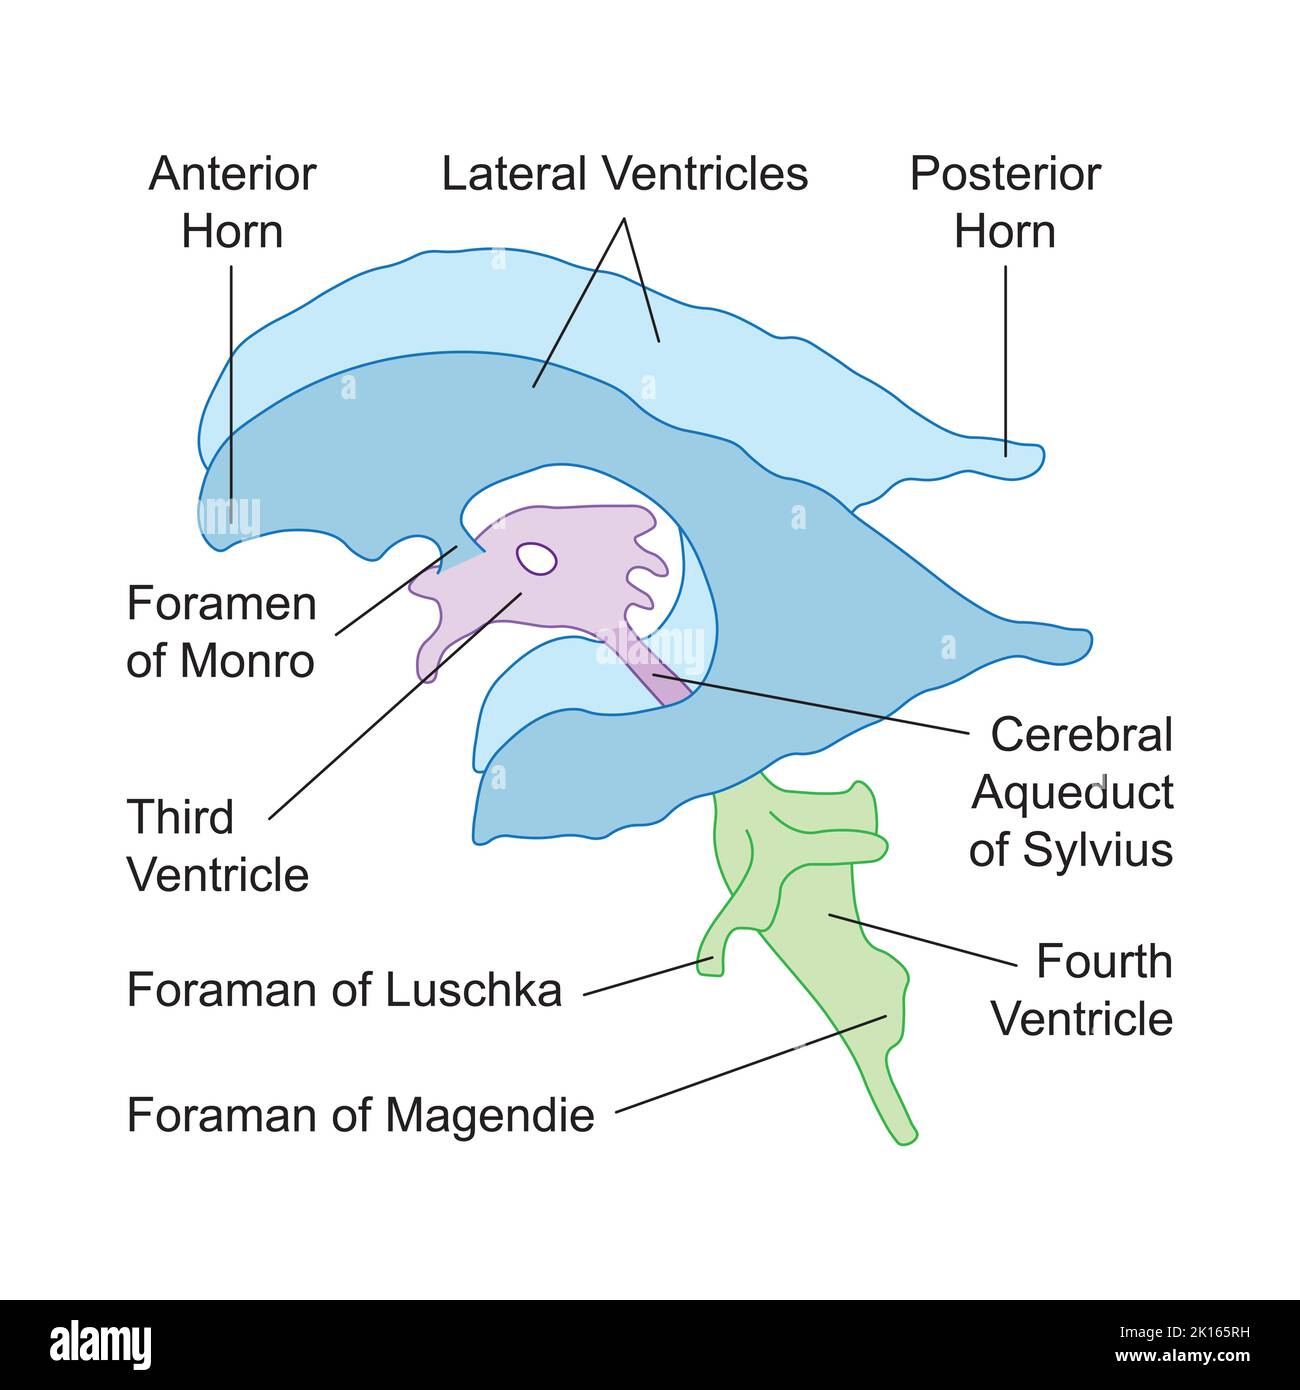

RF2K165RH–Wissenschaftliche Entwicklung des Ventrikulären Systems des Gehirns. Bunte Symbole. Vektorgrafik.

RM2AN4TWY–Handbuch der allgemeinen, beschreibenden und pathologische Anatomie (Band 2). Ventrikel, ein. Ventrikel des Kleinhirns, b. Aquädukt von Sylvius, C. Dritten Ventrikel, d. Lateralen Ventrikel, 1. Vordere Horn, 2. Hintere Horn, 3. Absteigend Horn, II. Textur, III. Gewicht, IV. Konsistenz, Kap. Iii. Umhüllt des Gehirns. Abt. Ich. Pia - mater, I. des Rückenmarks, II. Von Hirn, ein. - Externe Pia mater, b. Interne pia-mater, ich. Choroid Plexus des vierten Ventrikel, ii. Choroid Plexus des Großhirns, Art.ii.Apert-syndrom Membran, Art. hi. Dura-mater, I. spinalen Dura-mater, II. Zerebrale Dura-mater